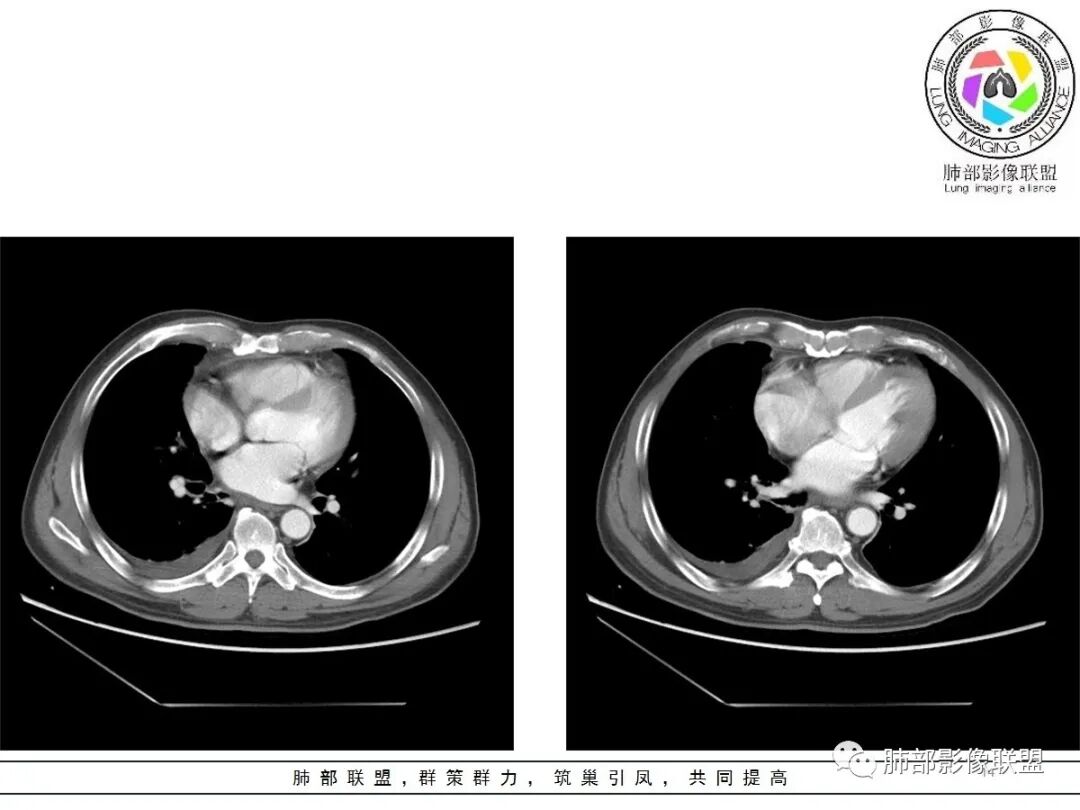

结果:符合B型胸腺瘤伴出血,坏死囊性变,局部脓肿形成

3.右上纵隔囊实性占位,边界清楚。中央见点状脂肪密度影,边缘见一点状钙化影,增强不均匀环形强化。

4.四天内病灶变化快,块影增大且不规则,包膜似不完整,边界不清,上份可见浸润或渗出,与周围心脏大血管及心包等间隙不清。胸水增多。

第一次的检查符合胸腺瘤影像学改变,短期内的形态学改变及突然出现的边界模糊或浸润等,符合出血或炎症。

胸腺瘤是前纵隔最常见的原发性肿瘤,男女比例为1∶1,发病高峰年龄在40~50岁,常伴有重症肌无力。胸腺瘤 WHO 分型为 A、AB、B、C 型,其中 A型和 AB 型为良性肿瘤,B 型包括 B1、B2、B3 三型, B1型为低度恶性,B2型为中度恶性,B3型和C型胸腺癌均为高度恶性,侵袭强,预后差。胸腺瘤组织形态学可伴有局部微囊变性,但胸腺瘤肿瘤区域出现广泛凝固性坏死、出血及囊性变则很少见,目前国内仅有 3 例报道,国外仅有少数文献报道。有学者将“广泛出血坏死、囊性变”描述为具有“自发退变”特征的胸腺瘤。现回顾性分析收治的 2 例具有“广泛出血坏死、囊性变”胸腺瘤的临床病理特征,并结合相关文献进行复习。

3 讨论胸腺瘤起源于胸腺上皮细胞,是前纵隔最常见的肿瘤。胸腺瘤病因未明,成人多发,儿童很少见。根据上皮细胞形态及上皮细胞与淋巴细胞的比例,把胸腺瘤分为 A 型、AB 型、B 型(B1、B2、B3) 和C型(胸腺癌)。临床常用Masaoka分期来判断疾病的进展和预后,胸腺瘤治疗主要有手术治疗、放射治疗和化疗等。胸腺瘤伴有局部微囊结构比较常见,但肿瘤组织出现大片的凝固性坏死,广泛出血囊性变,仅残留少量的肿瘤细胞,这种形态特征很少见。查阅以往文献也仅有几篇相关报道,目前WHO胸腺瘤分类中还没有把具有这种特征的胸腺瘤归为新的一类。Wright 等[1]和 Hori 等[2]回顾分析并报道了4例伴有广泛凝固性坏死及出血的胸腺瘤(WHO 分型为 B1,B2,B3 和 AB 型),患者出现严重的胸痛,临床上容易误诊为淋巴瘤和侵袭性胸腺瘤 ,分 别 随 访 9~90 个 月 ,这 些 患 者 预 后 良 好 。Moran[3]报道了 25例具有显著出血囊性变及坏死的胸腺瘤,患者年龄18~73岁,中位年龄45.5岁,男性14例,女性11例,9例患者无临床症状,16例患者出现胸痛、咳嗽。随访了 14 例患者,随访时间 1~18年,中位随访时间 9年,11例患者健在,无肿瘤复发和转移,3例患者死于其它疾病。和其它肿瘤不同,胸腺瘤伴有广泛坏死并不象征肿瘤恶性程度增加和病程进展。这种广泛坏死可能与血管畸形,动脉管壁增厚、管腔狭窄、血栓形成所致的血供不足有关。本文总结的例1胸腺瘤广泛坏死区周边囊壁出现了多个管壁玻璃样变性、增厚的畸形血管,管腔扩张,加之患者有 10 年高血压病史,出现的这种坏死可能与血管病变导致的血流动力学异常有关。此外,Gray[4]和 Okagawa 等[5]也分别报道了 1 例 B2 胸腺瘤出现广泛坏死,肿瘤退变,胸水消失。肿瘤发生退变可能与患者体内类固醇激素的水平改变有关。肿瘤出现的广泛出血坏死、囊性变这些形态学特点可能是胸腺上皮细胞和微环境相互作用所致的炎症反应性改变,这种坏死可能是一种梗死。国内报道的具有这种广泛坏死囊性变特征的胸腺瘤较少,目前仅有3例报道。李剑[6]报道了2例胸腺瘤伴有广泛凝固性坏死,病理诊断为 B2 和 B3型胸腺瘤,随访 10 个月和 8 个月,患者均无复发和转移。白锡山等[7]报道了 1 例右上纵隔巨大胸腺瘤·199·Surg Res N Tech Vol.5 No.3 Sep,2016坏死继发囊肿,起初被误诊为肺结核。因此,伴有广泛坏死囊性变的胸腺瘤一定要广泛取材,以免漏掉残存的少量肿瘤组织,导致误诊漏诊。本研究复习了我院 2008 年至 2015 年所有的胸腺瘤、胸腺癌病例,发现了 2 例具有所谓的自发退变特征的胸腺瘤,其中 1 例有胸膜侵犯,Masaoka 分期Ⅲ期,随访 28 个月,预后良好。这种侵袭性胸腺瘤出现的广泛出血坏死、囊性变是否真正代表肿瘤发生退变及良好的预后,尚需要更多的临床资料积累及延长随访时间评价这类患者的预后。具有这种特征的胸腺瘤少见,影像学检查发现的前纵隔巨大肿瘤伴有胸膜、心包膜侵犯或出现胸水,可能诊断为恶性进展期胸腺瘤,不能进行手术治疗。但在临床工作中,我们要把这种带有“自发退变”特征的胸腺瘤考虑到鉴别诊断中,以免延误患者治疗。具有这种形态学特征的胸腺瘤切记一定要广泛取材,以免漏诊误诊。